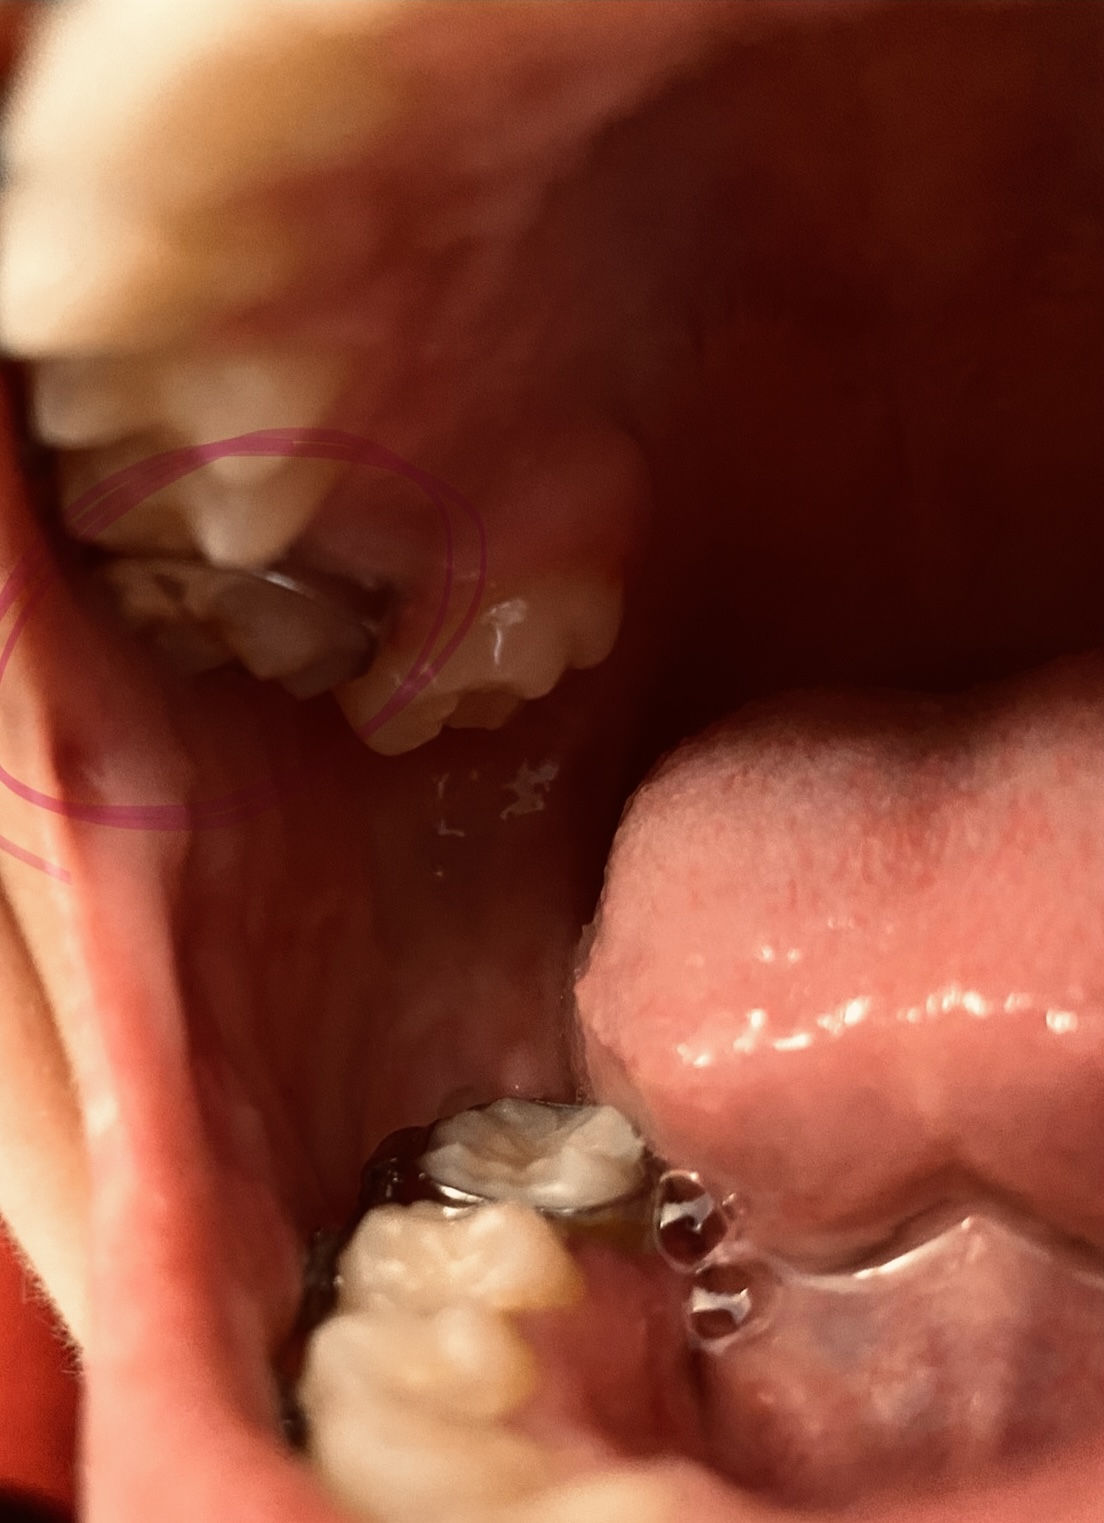

I have a baby lateral incisor that never fell out and my canine has fully grown in above my gum line, almost looking like it’s completely into of my gums. How would I go about fixing this bite? Are invisible aligners able to bring a tooth like this down and into place?

You are a great candidate for orthodontic treatment. From the picture, without seeing your molars or your natural occlusion, it is hard to see what bite classification you fall into. If your molars align properly, clear aligner therapy may be an option. However, if your natural bite is open, as pictured, traditional orthodontic treatment may be necessary. It is best to schedule a consultation with a dentist or orthodontist who provides both clear aligner therapy and traditional orthodontic options. He/she can best guide your decision based upon not only your current occlusion, but your treatment goals as well.